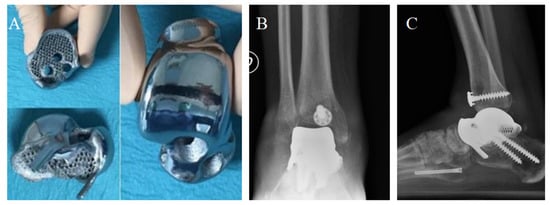

A TTR was planned and realized by the Canary Islands Institute of Technology as an exact reproduction of the shape and size of the original talus. A CT scan and volume rendering of the enucleated talus was sent to the institute, where the artificial talus was created by electron beam melting (EBM ARCAM S12, Arcam AB, Mölndal, Sweden). Electron beam melting is a 3D printing process effective and validated for the production of titanium orthopedic implants) [].

The prosthetic implant was made of trabecular titanium Ti6Al4V, weighing only 78 g, with smooth and chrome-covered tibial, fibular, and navicular joint surfaces. The calcaneal surface was kept porous to ensure the best adhesion of the talo-calcaneal surfaces.

Four channels were carved at the level of the talus neck to fit the screws and allow ligament reconstruction. Two months after the accident, the prosthetic replacement and ligament reconstruction was finally performed by exposing the cement spacer through an anteromedial longitudinal approach. After cement removal, a customized guide was used to prepare the upper surface of the calcaneal bone according to preoperative planning. The talar prosthesis was fixed to the calcaneus by two screws. Antero-medial capsule-ligamentous reconstruction was performed using a peroneus brevis tendon allograft inserted at the level of the talus foramen and stabilized at the tibial level with a transosseous tunnel and Soft Tissue Anchoring System (CONMED) (Figure 8).

Figure 8.

The prosthesis ready to be implanted (A). X-ray of the implant from antero-posterior (B) and latero-lateral (C) projections. Articular space can be observed in figure (B).